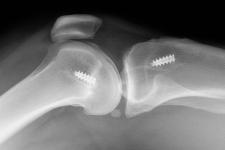

ACL Tear Treatments - ACL Surgery

The ACL or anterior cruciate ligament is one of four key knee ligaments. The ACL attaches the tibia to the femur, keeping the shin bone in place, and is critically important to knee movement and stability. An ACL strain or tear is one of the most common knee injuries and individuals who have suffered an ACL injury often complain that their knee "gives out" or buckles as the joint's overall stability has been compromised. While there are many, many ways to tears